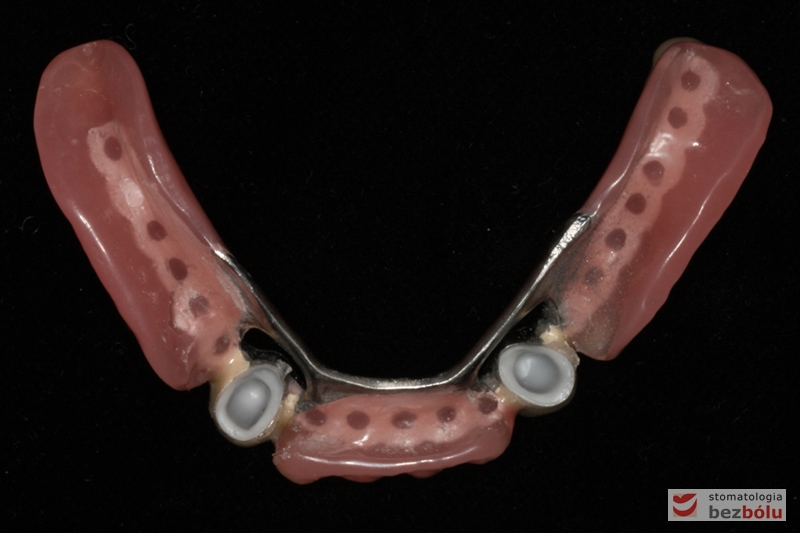

Odbudowa protetyczna w żuchwie - precyzyjne dopasowanie pracy protetycznej do podłoża

Odbudowa protetyczna w żuchwie – precyzyjne dopasowanie pracy protetycznej do podłoża

Odbudowa protetyczna w żuchwie - precyzyjne dopasowanie pracy pottetycznej do podłoża

Odbudowa protetyczna w żuchwie – precyzyjne dopasowanie pracy pottetycznej do podłoża